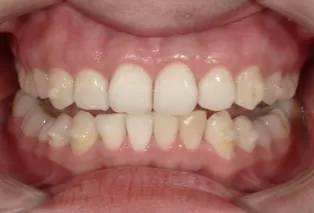

Après traitement

Photos faciales avant le traitement